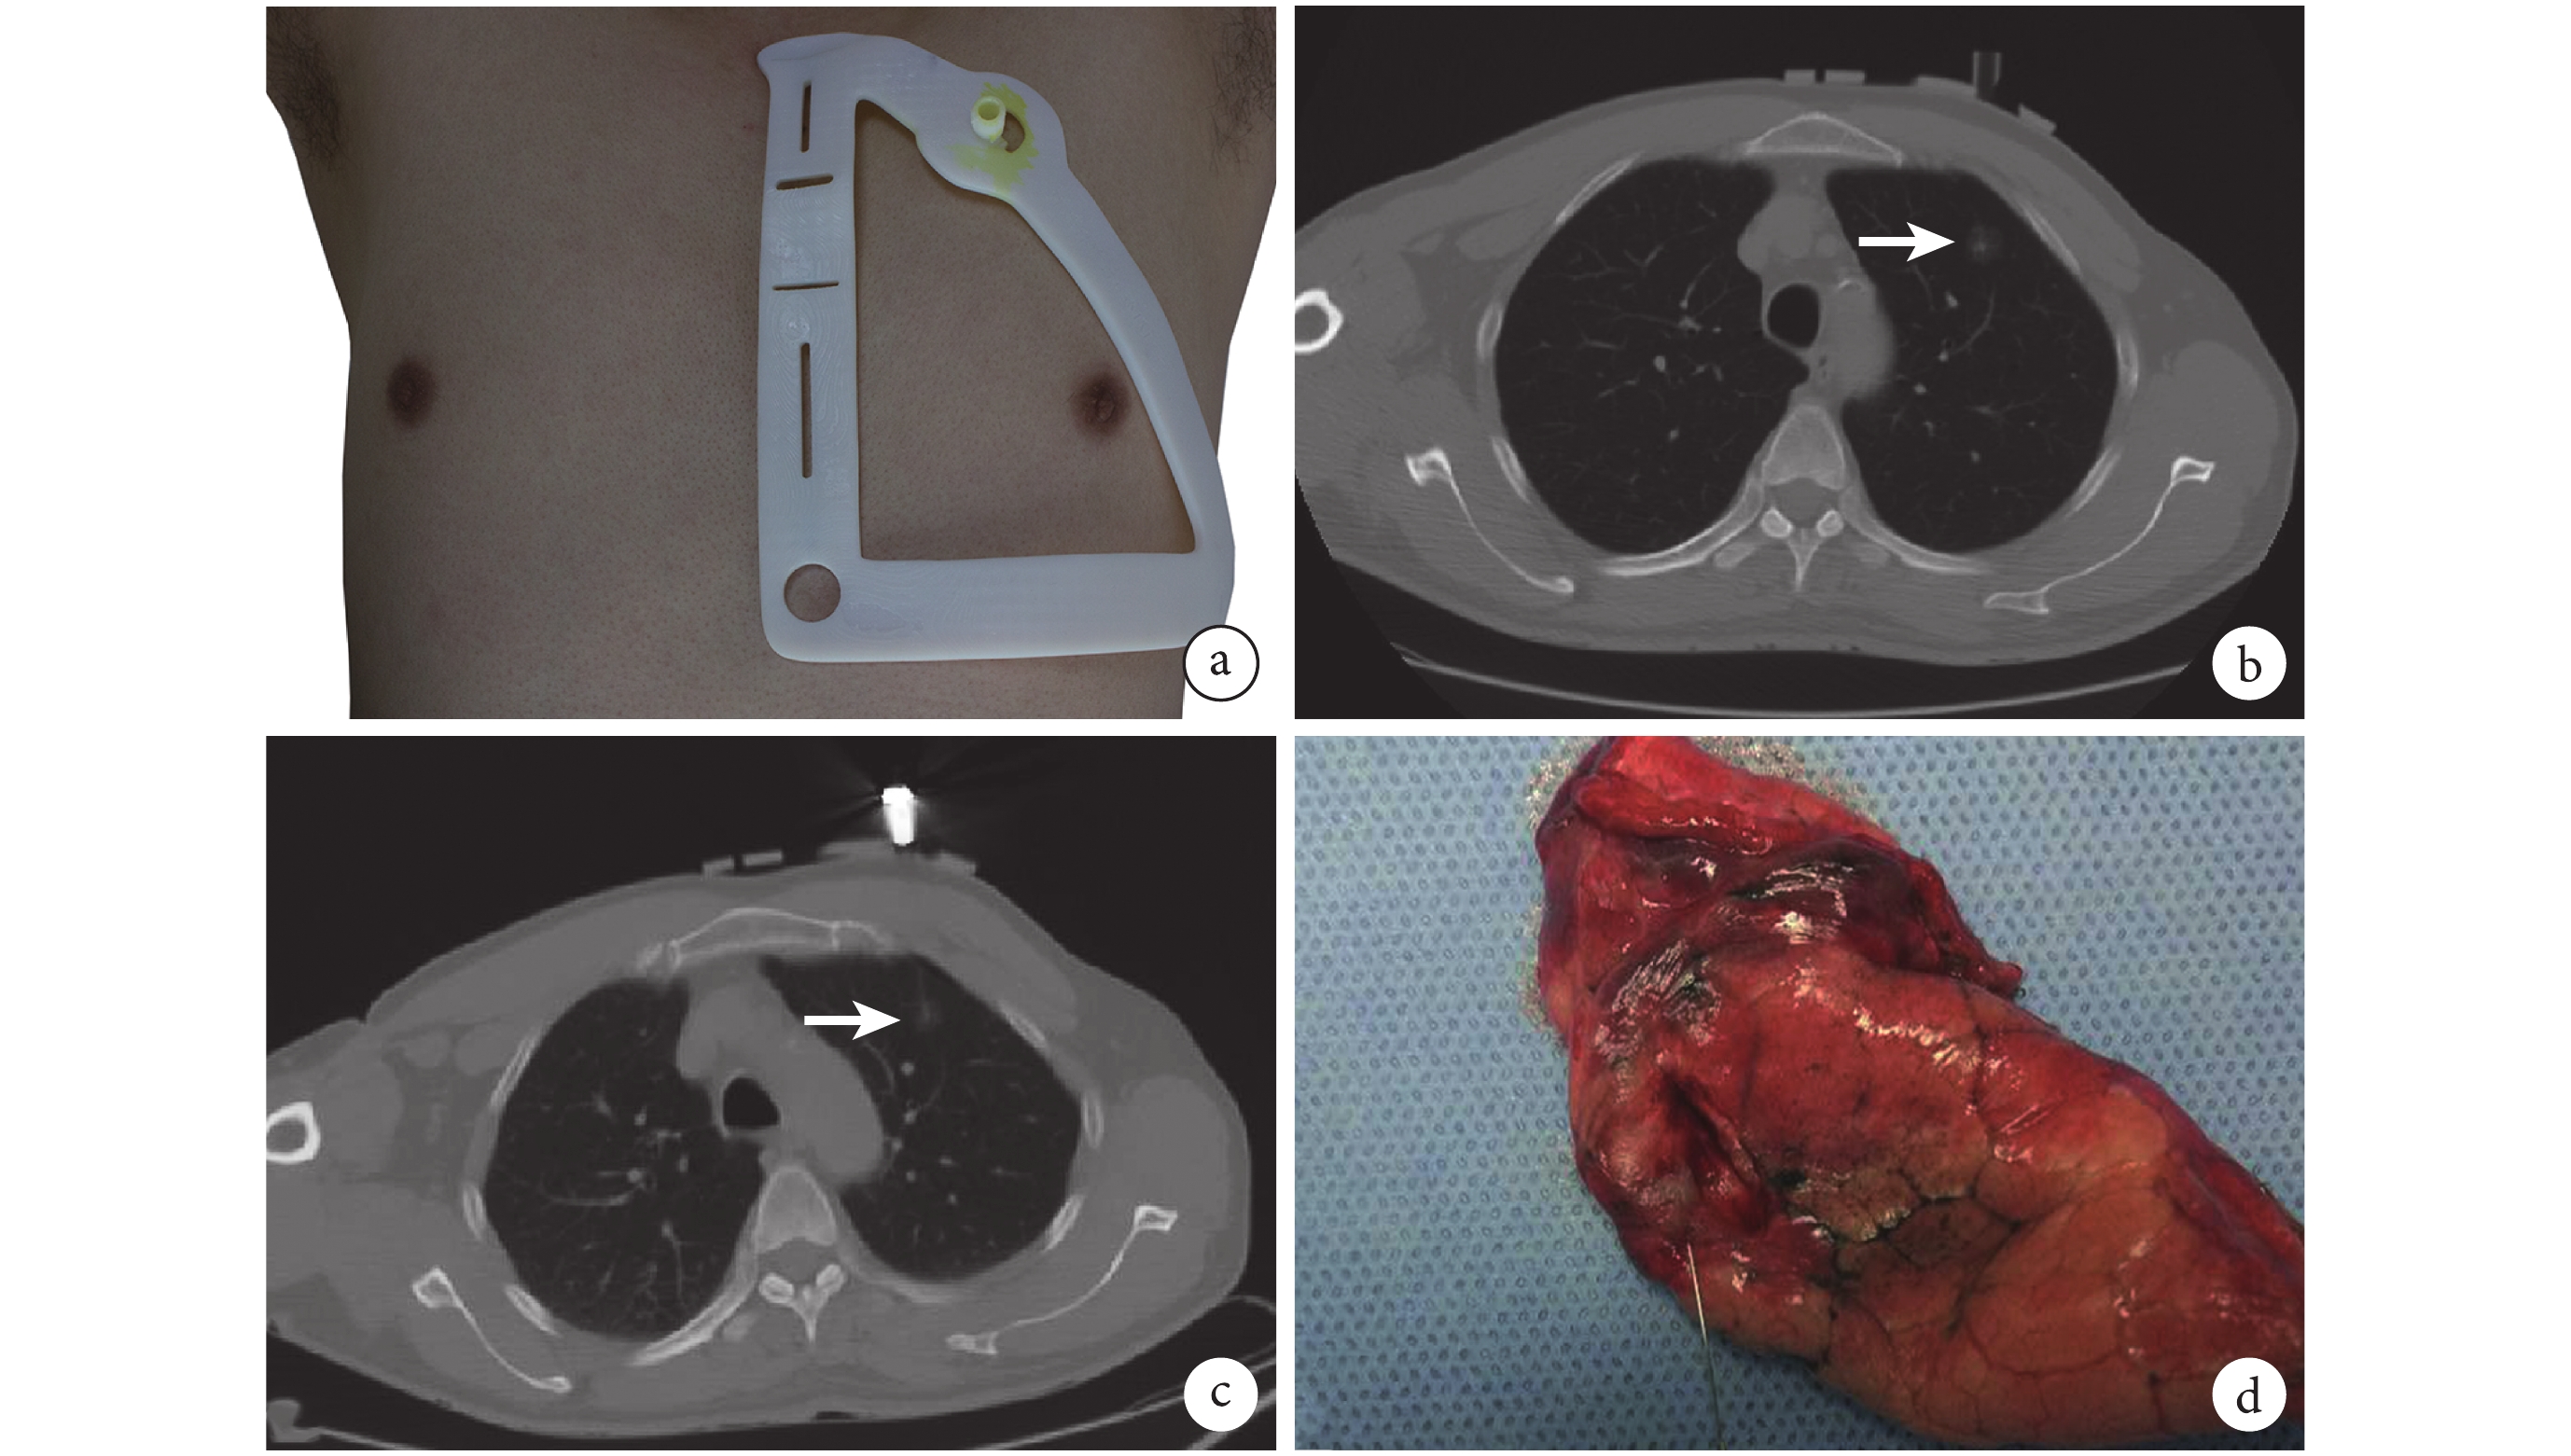

目前經皮肺穿刺定位需要在CT實時引導、監視下,由外科/影像介入醫師,根據患者二維CT圖像,及時規劃穿刺路徑,手動掌握穿刺角度。因此,在實際操作中,為實現穿刺針準確“命中”結節,患者往往需要接受多次CT掃描,輻射暴露風險明顯增加;同時,在穿刺過程中,穿刺針的反復調整則明顯增加氣胸、出血等并發癥的發生率。為降低經皮肺穿刺定位對于CT的依賴,簡化經皮肺穿刺操作流程,Zhang 等[5]根據患者術前CT信息,利用3D打印技術,設計了一種個性化穿刺定位導板。該導板預先標記穿刺針位置與角度,操作者根據患者體表解剖標志放置導板,然后根據導板標記位置完成定位穿刺;見圖1。

a:導板放置;b:第一次CT掃描,箭頭處為靶灶;c:穿刺后CT掃描,箭頭處為靶灶;d:手術切除標本

前期臨床試驗結果顯示[5],導板輔助肺穿刺定位可明顯簡化經皮肺穿刺定位流程,降低CT掃描劑量。由于結節位置受呼吸、體位等因素影響,導板輔助定位同樣存在一定偏差,結果提示穿刺針偏差局限于2 cm以內,可成功指導VATS術中肺結節識別。為進一步驗證導板輔助定位的有效性與安全性,前瞻性隨機對照臨床試驗(NCT02952261)已注冊開展。